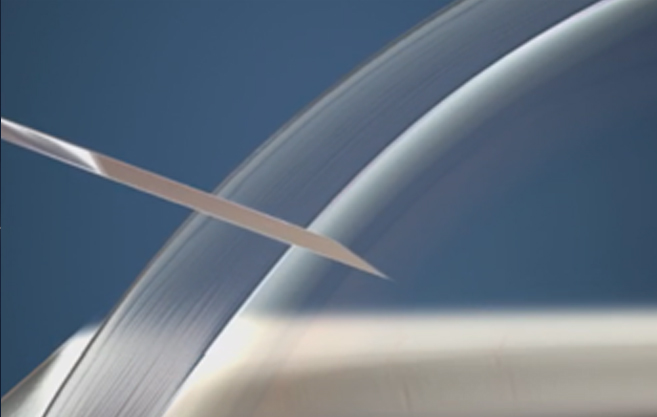

프리미엄 레이저 120º 다면 절개를 이용한

절개부위의 고정으로 충격에 강합니다.

절개 부위가 고정된

레이저 다면 절개